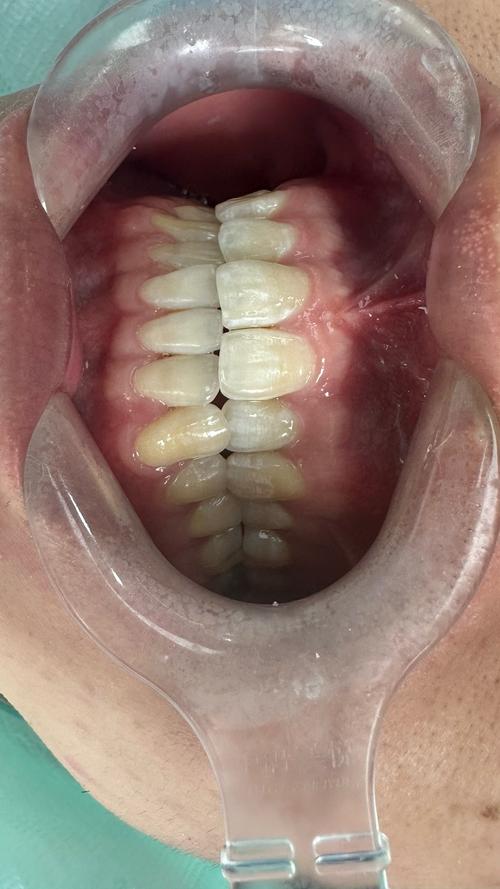

(图片来源网络,侵删)